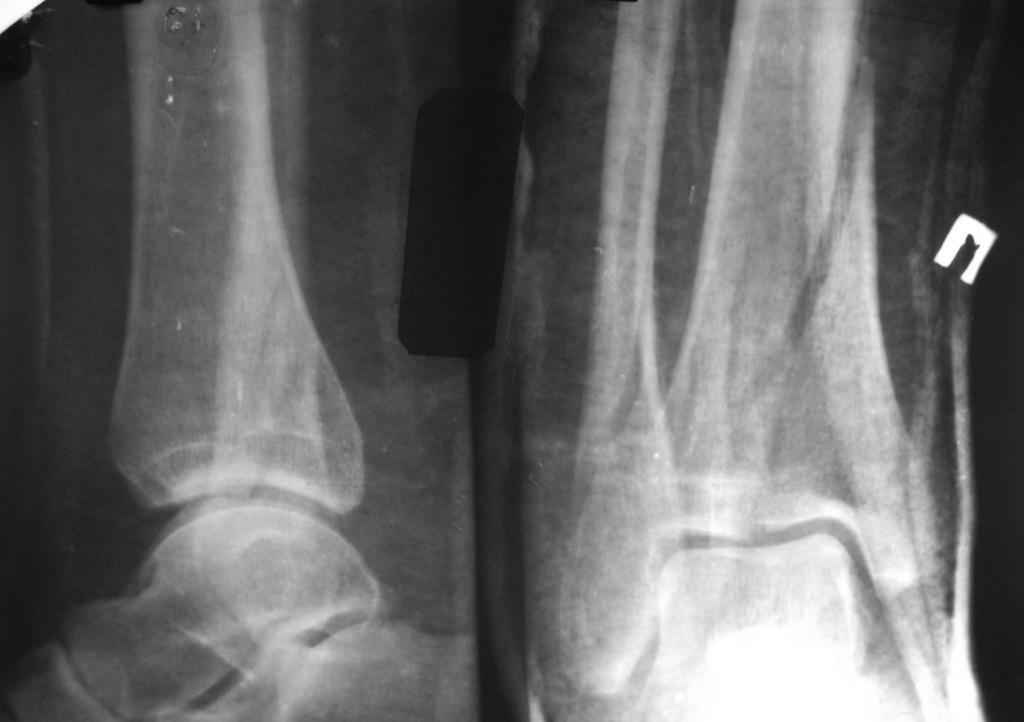

прошу прощения за то, что забыл приложить снимки